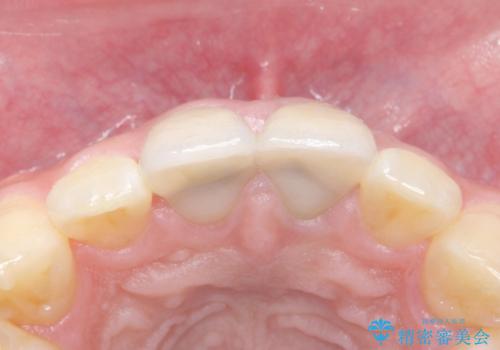

歯のガタつきも解消することができました。

e-maxクラウンでは仮着ができませんが、今回は一回でご満足いただける修復ができました。